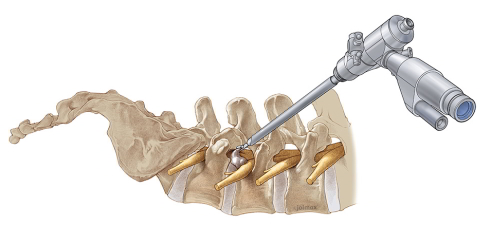

Spine Surgery

We provide comprehensive surgical care for degenerative, traumatic, and tumour-related spinal conditions. This includes intradural and extramedullary tumours, bone metastasis surgery, and structural procedures for instability, disc problems, fractures, and spinal deformities like scoliosis. Treatments use techniques ranging from traditional open surgery to minimally invasive and robotic approaches, including spinal fusion and laminectomy, with the goal of stabilizing the spine, relieving pain, improving mobility, and supporting neurological recovery.